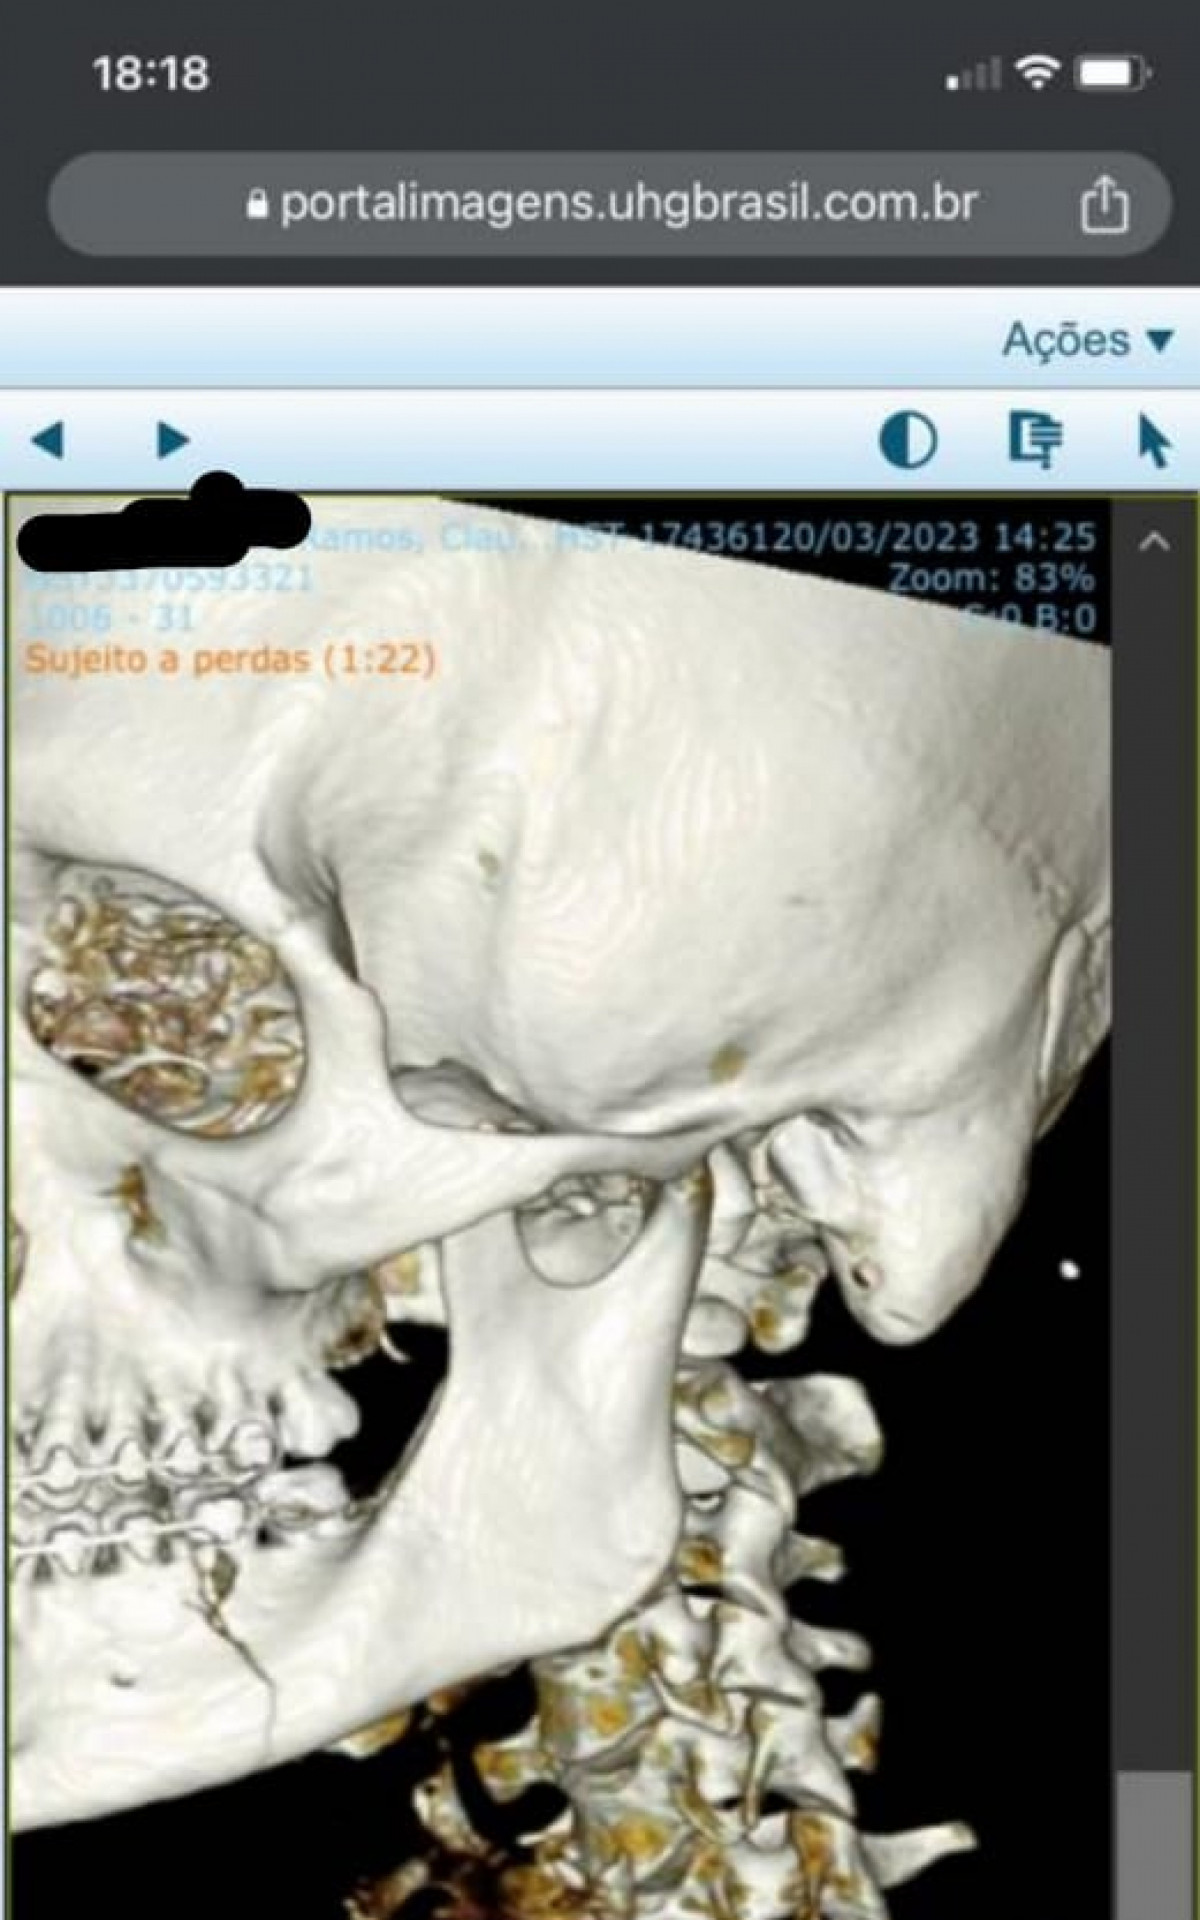

Tomografia de Cláudio Ramos confirma fratura no maxilar após agressões - Foto: Arquivo pessoal

Tomografia de Cláudio Ramos confirma fratura no maxilar após agressõesFoto: Arquivo pessoal

Rio - O torcedor do Vasco Cláudio Ramos, de 30 anos, foi agredido por quatro torcedores do Flamengo quando estava a caminho do Clássico dos Milhões, disputado no último domingo (19), no Maracanã, pela semifinal do Campeonato Carioca. Após levar golpes no rosto, ele passou por exames no hospital que confirmaram fraturas nos dois lados do maxilar e terá que passar por uma cirurgia de emergência.